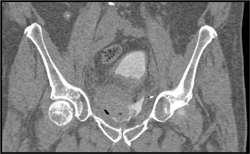

Diagnosis

Post-op Abdominal Wall